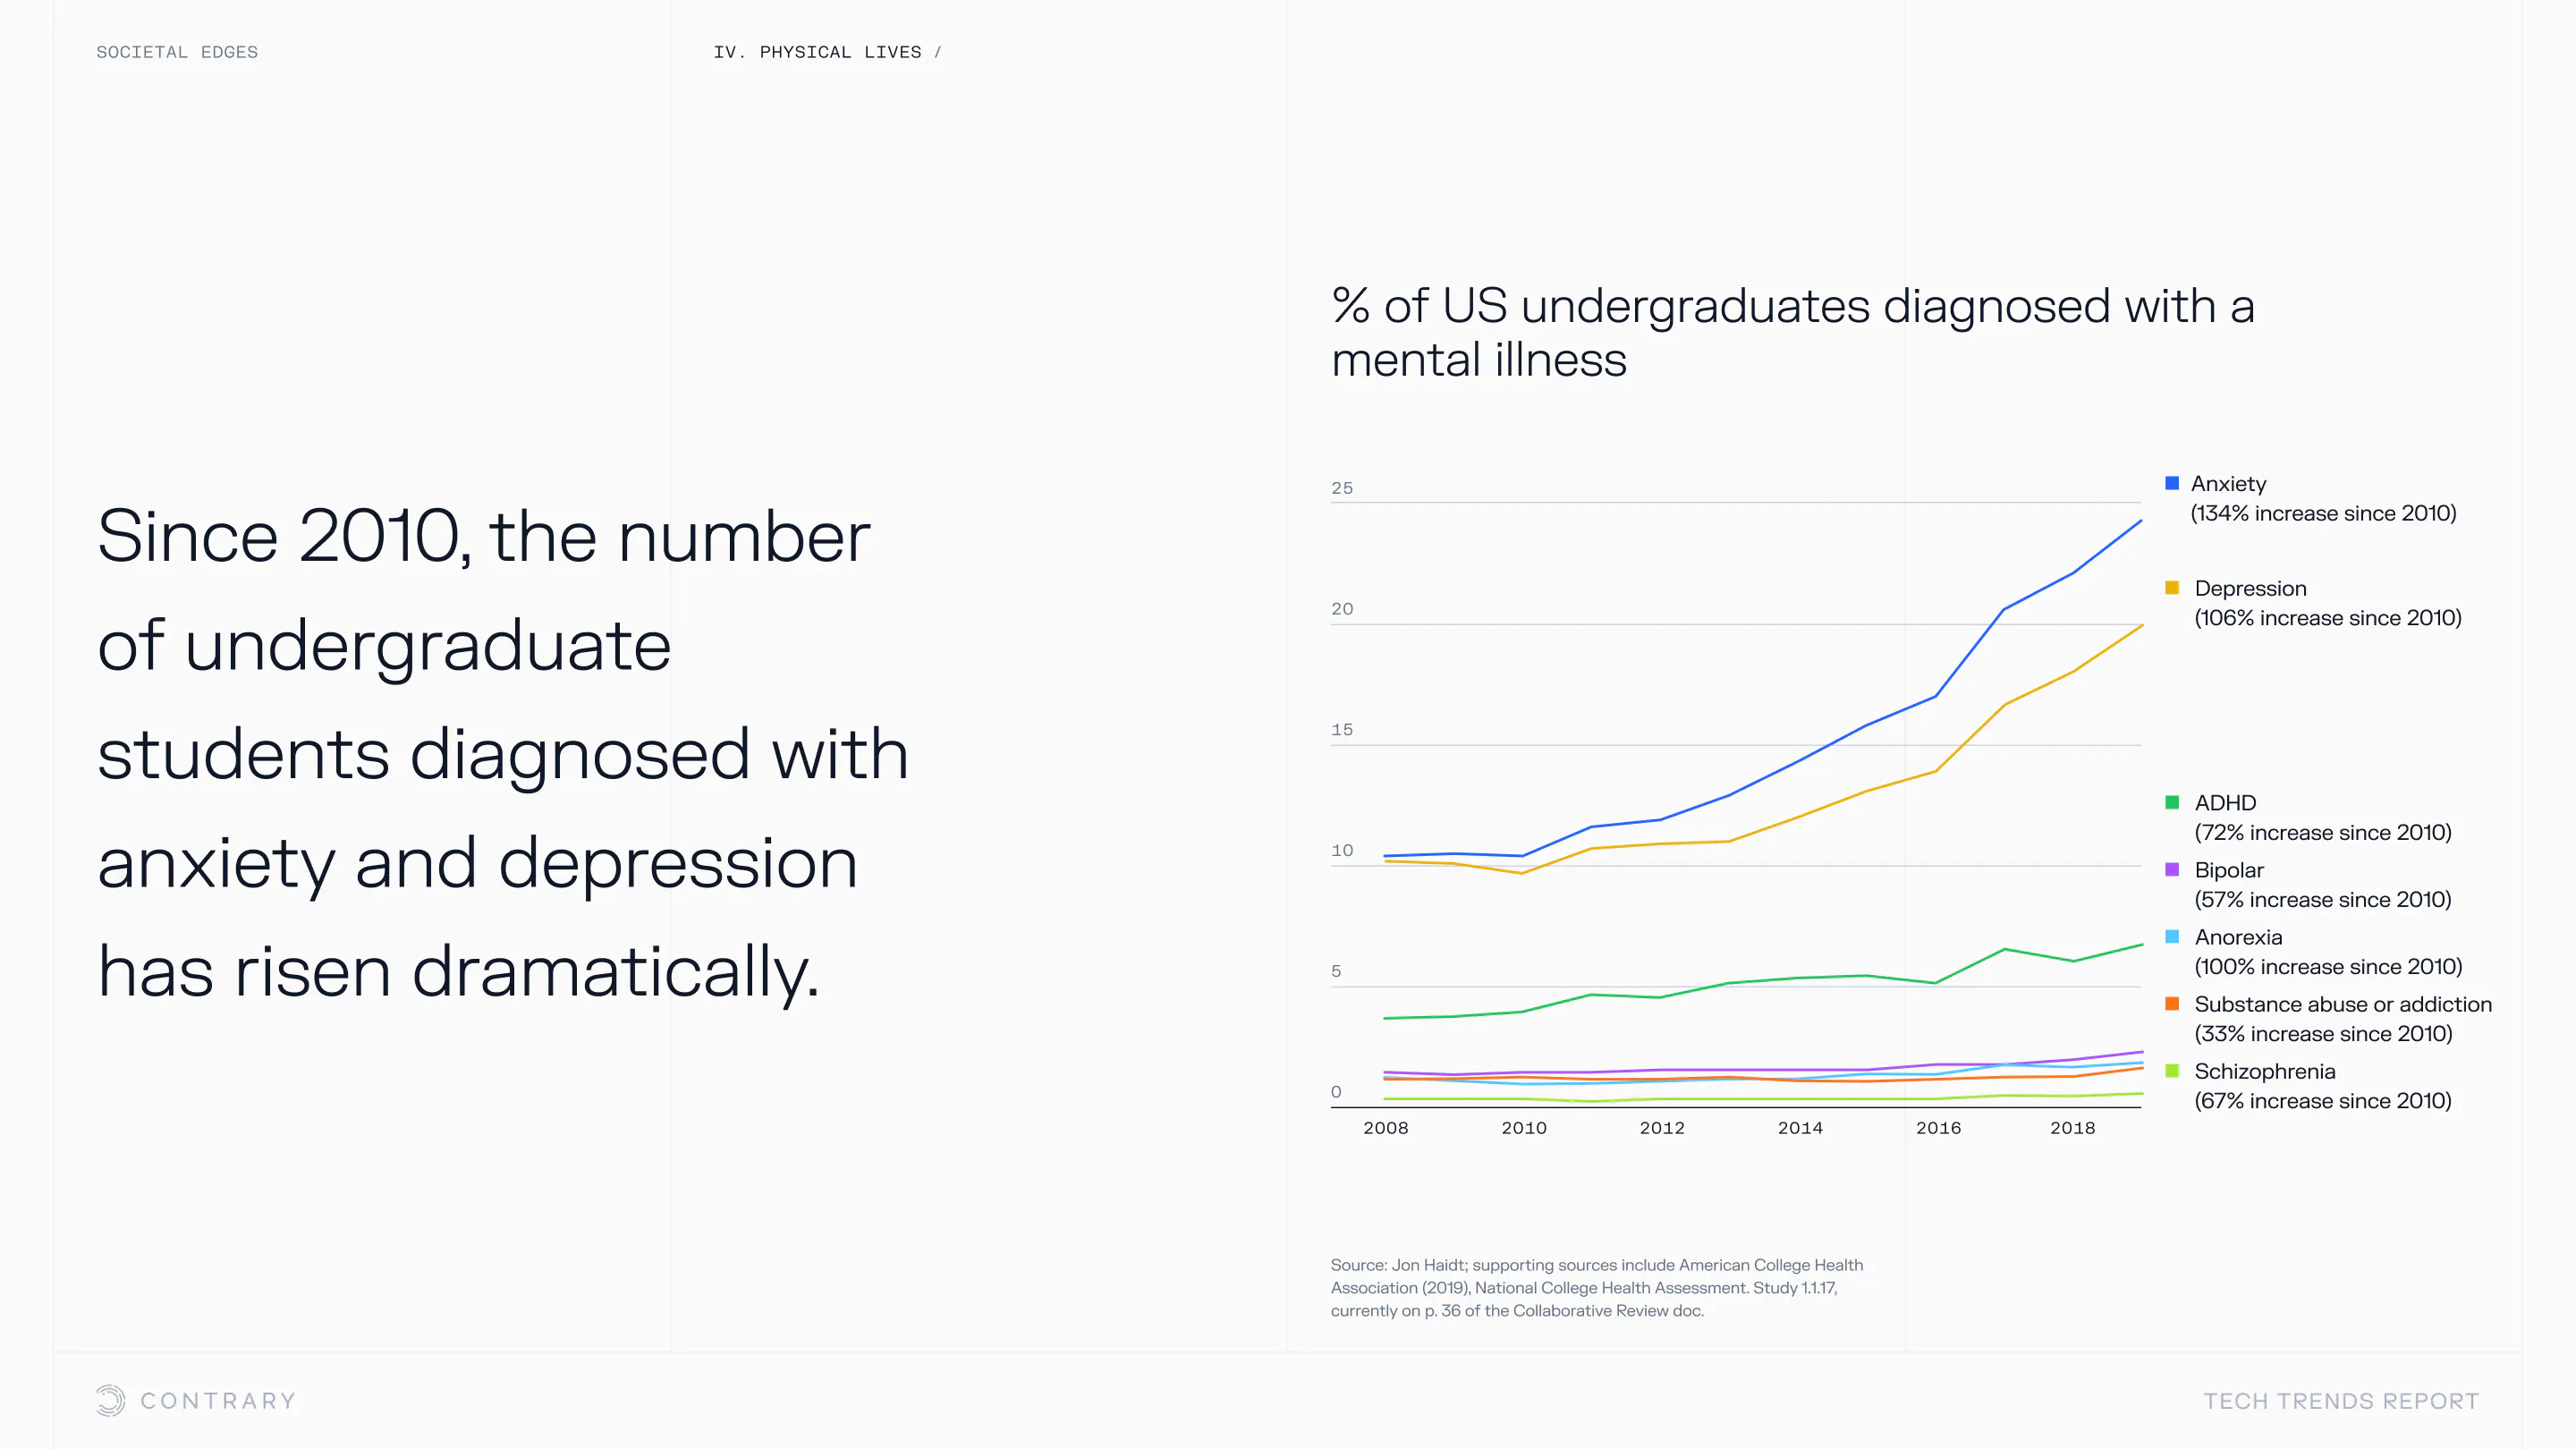

An aging population is bringing up a range of increased concerns, from mental health to disease control. Obesity and gastrointestinal cancers are plaguing younger generations. The cutting edge is tackling a system that has unhealthiness woven into it.